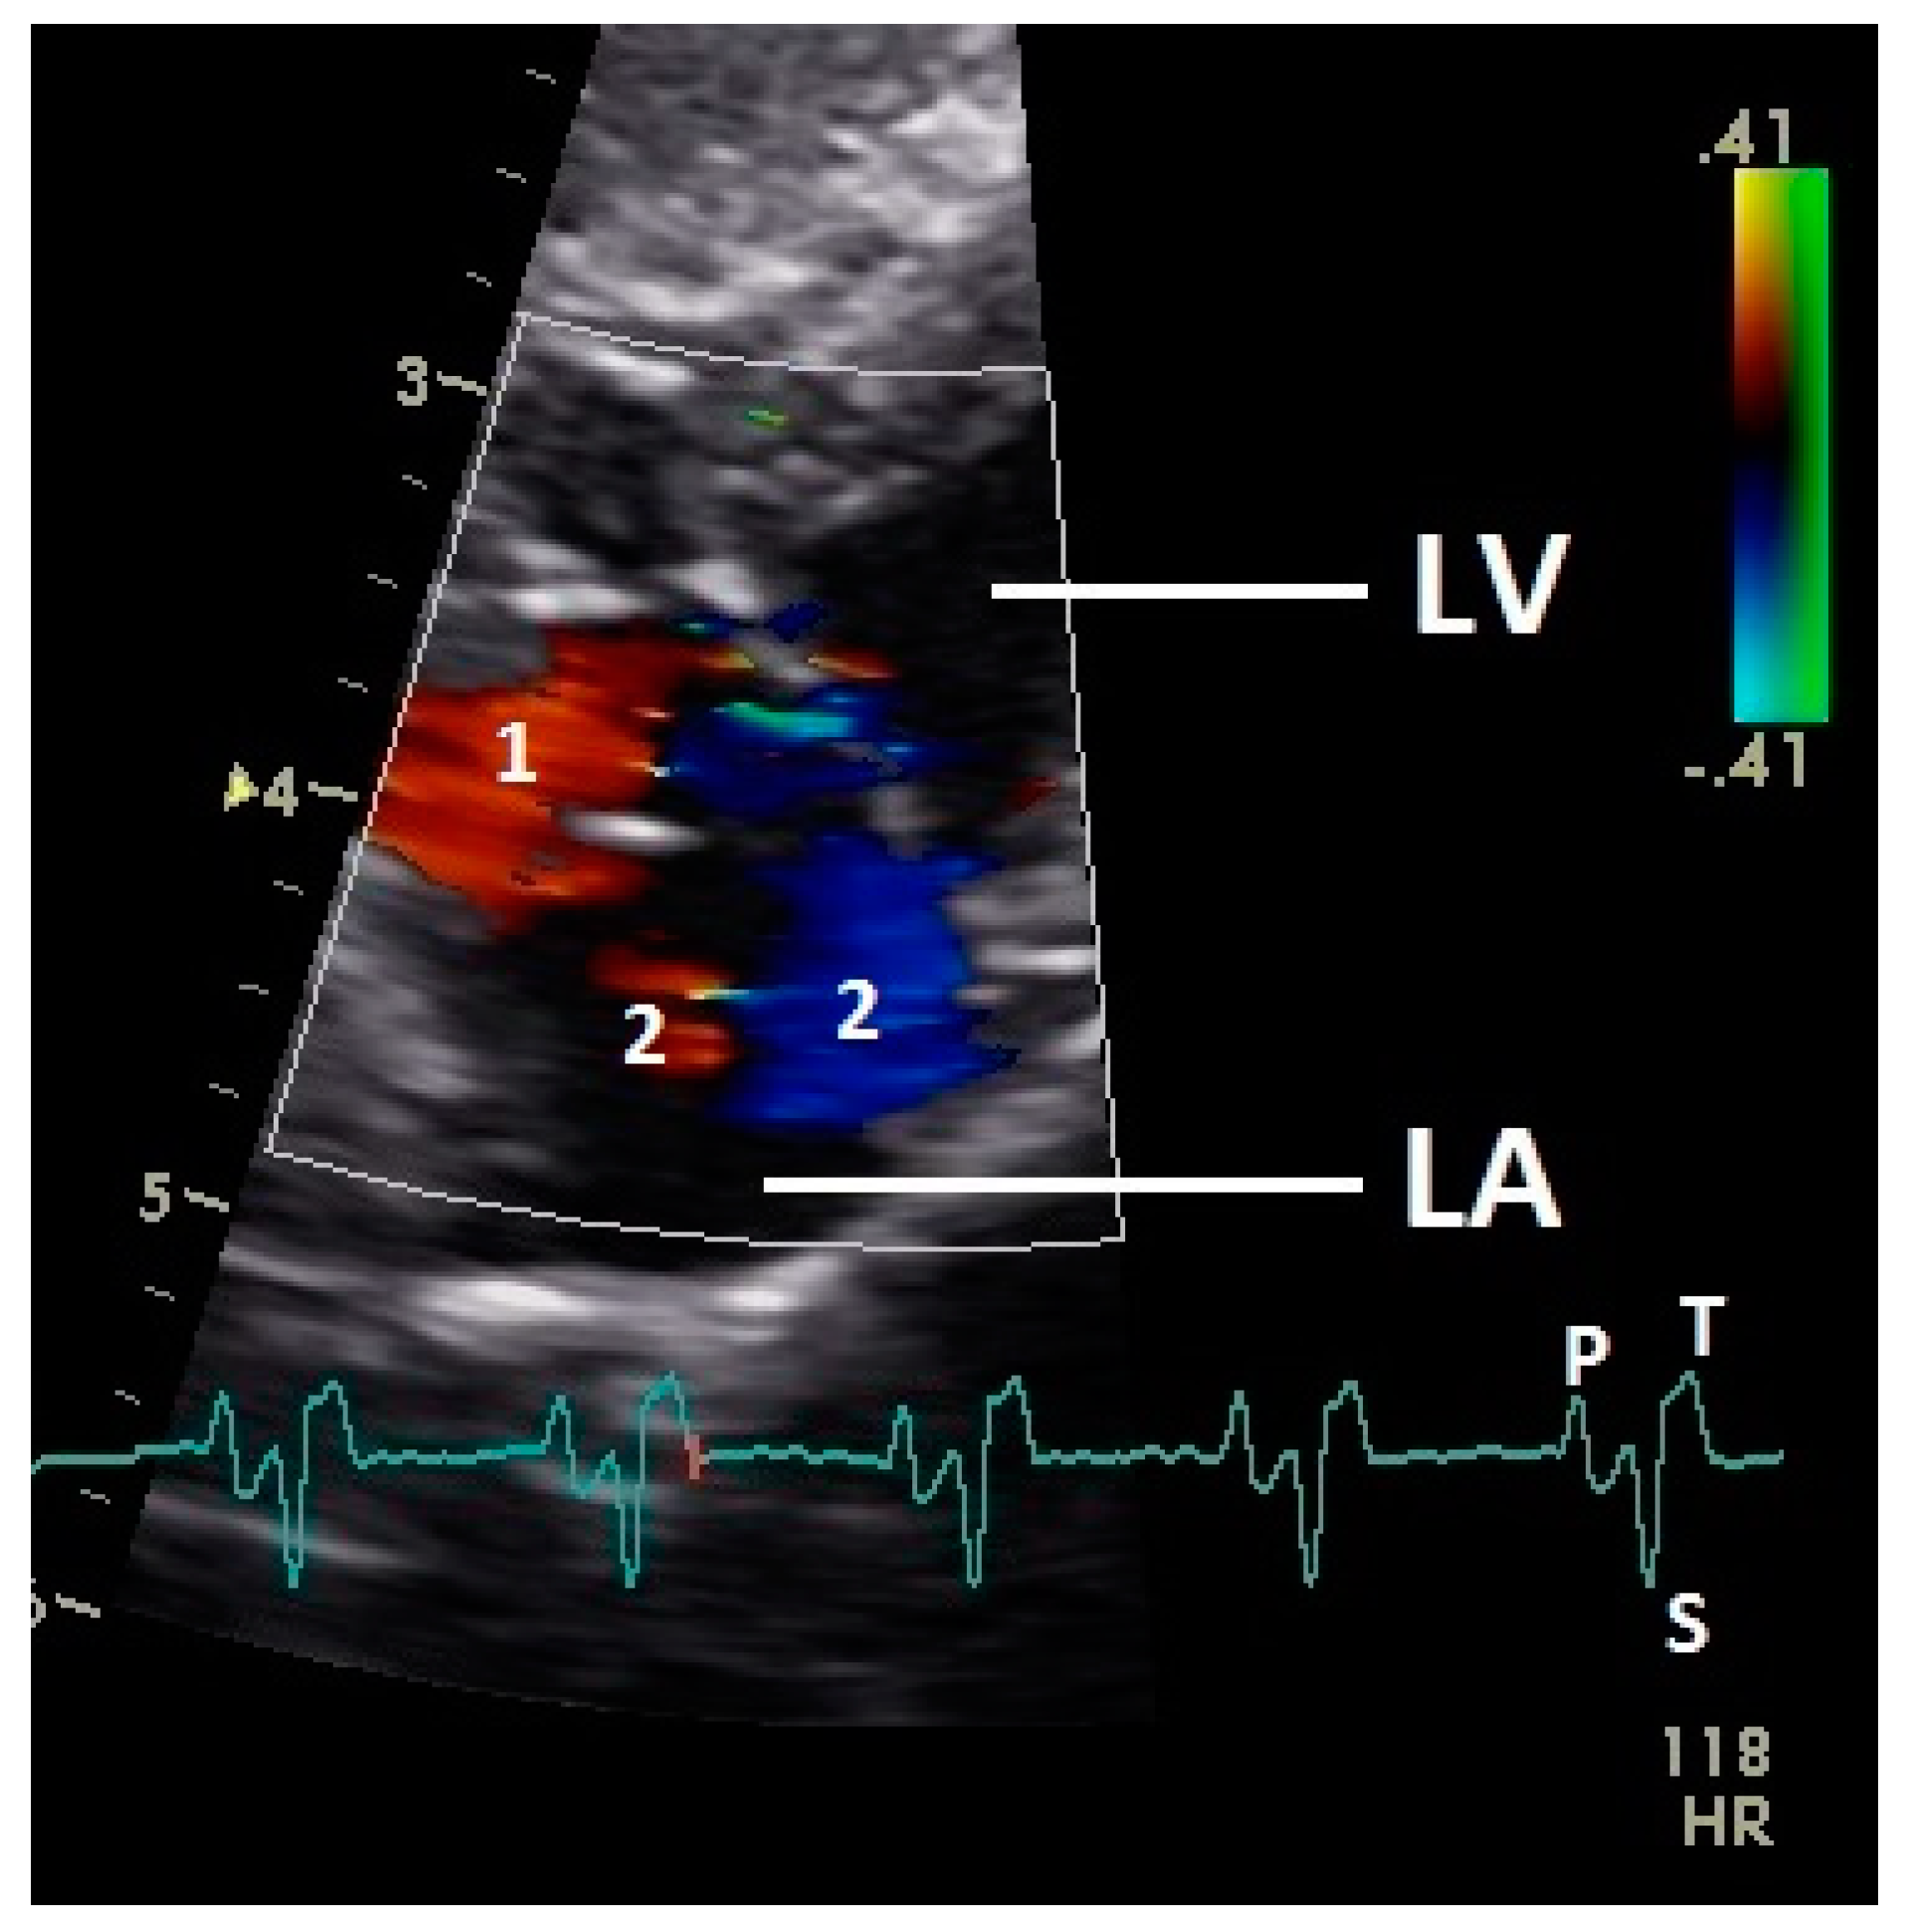

After the P wave of the ECG in the phase of the relaxation of myocardium of the left atrium, a little blue filling signal over the AV valve was seen in the some pigeons (n = 27; 62.8%) with the used settings (Figure 5). In all pigeons a later and faster blue inflow signal in the atrium in the time of the descending part of the T wave was recorded over the AV valve to the left part of the atrium (significant difference Chi-squared test p ≤ 0.001). At the same time a red signal was seen right and left from the valva pulmonis in some pigeons (25 out of 43 birds; 58.1%; Figure 6). The position of the valva pulmonis was almost constant in diastole (Figure 7) and systole (Figure 5 and Figure 6).

Figure 6.

Color Doppler image of the late blood inflow in the left atrium (red signal; 1) and blood flow vortex formation (2). LV: left ventricle; LA: left atrium; HR: heart rate. Electrocardiogram: P: P wave, S: S wave, T: T wave. The color scale on the right of the image is calibrated in m s−1.

Constant simultaneous occurrences of red and blue color in the Doppler images of ventricles and atria show the presence of typical constant blood flow vortex formations in the avian heart, comparable to the mammalian heart [32]. Vortices in the cardiovascular system are supposed to play fundamental roles in normal physiology and provide a proper balance between blood motion and the stresses on the surrounding tissues [32]. In the color Doppler examinations of the pigeon heart in the “four-chamber view”, a vortex clockwise in the left atrium and counter-clockwise in the right atrium were observed. In this context the valva pulmonis of the left atrium is discussed as an important anatomical structure for sealing the atrial cavum [1]. However, the color Doppler images in our investigation show that in diastole (atrial contraction) and systole (atrial filling) the position of the valva pulmonis is very constant. There is no evidence for a motion of this valve which could contribute to the closure of the left atrium (see Figure 5, Figure 6 and Figure 7). The main function of this anatomical structure seems to be to direct blood flow towards the left ventricle (see Figure 6). The passive filling of the atria was visible after the P wave of the ECG as a cause of the relaxation of the myocardium and in the time of the end of the T wave of the ECG as a cause of the ventricular pump mechanism by the myocardial contraction in the systole. The findings in the color Doppler sonographic examination of the ventricles allow the conclusion of the presence of an asymmetric vortex ring in the left ventricle in the passive and active ventricular filling with a stronger vortex behind the longer septal part of the left AV valve (see Figure 1, Figure 2 and Figure 3). It is possible that an asymmetric valve shape allows a typical vortex formation (larger vortex in the direction of the outflow tract) that enables a faster blood flow and emptying of the ventricle [33]. Similar vortex formations in the left ventricle are described in the mammalian heart [32,33]. In the right ventricle the active ventricular filling leads to a great counter-clockwise blood vortex in this ventricle. The blood flow behind the right AV valve in the active ventricular filling as well as the active movement of this muscular valve during the closure seem to be important for the development of this blood flow vortex (see Figure 8). In connection with the asymmetrical shape of the right ventricle and oblique arrangement of the right AV valve [1], the shape of the blood vortex simplifies the outflow of blood through the pulmonary artery.